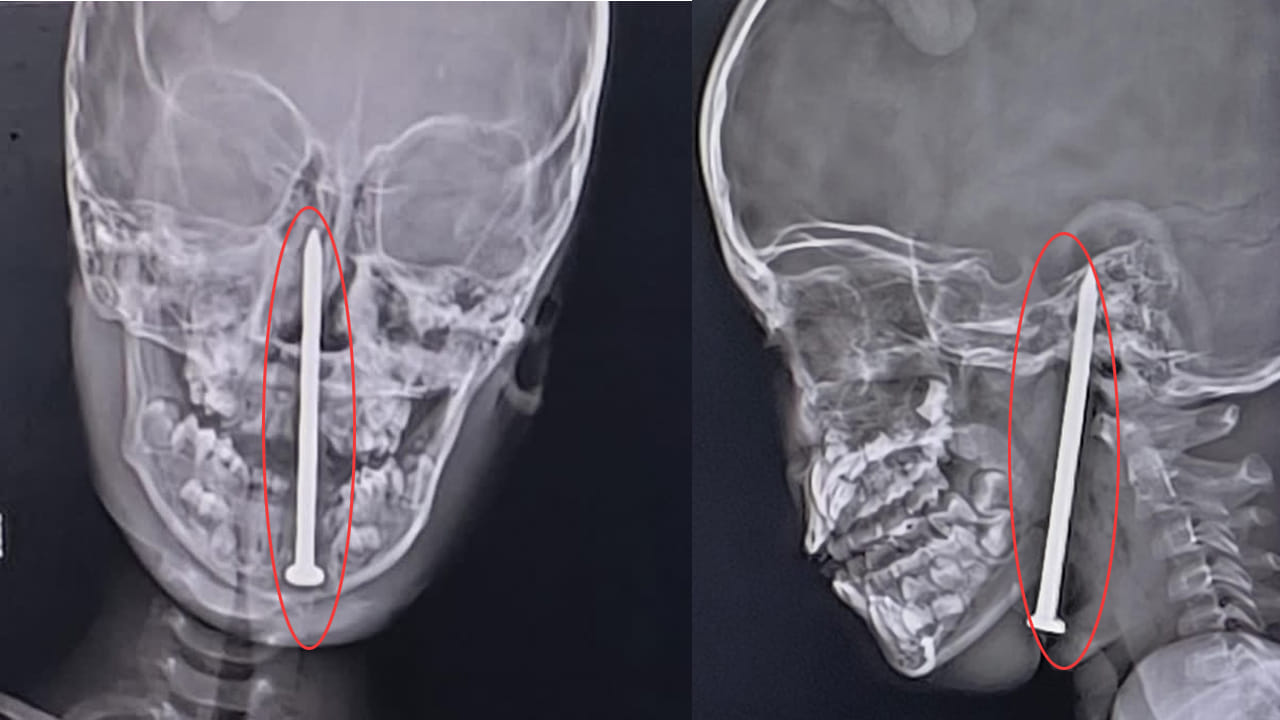

లక్నోలోని కింగ్ జార్జ్ మెడికల్ యూనివర్సిటీ (KGMU) వైద్యులు అరుదైన శస్త్రచికిత్సను విజయవంతంగా చేసి, 7 ఏళ్ల బాలుడి మెదడులోకి మెడ ద్వారా వెళ్లిన 8 సెంటీమీటర్ల ఇనుప మేకును తొలగించారు. ఈ శస్త్రచికిత్స దాదాపు 10 గంటలపాటు సాగింది.

బాలుడు ఉత్తరప్రదేశ్లోని బలరాంపుర్ జిల్లాలోని నవాజ్పుర్ గ్రామానికి చెందినవాడు. మే 15న ఆడుకుంటున్నప్పుడు కిందపడిపోయి, మెడలోకి మేకు దూసుకెళ్లింది. అది మెదడుకు వెళ్లి అక్కడే కూరుకుపోయింది. కుటుంబ సభ్యులు మొదట అతడిని ప్రైవేట్ ఆసుపత్రికి, ఆపై బలరాంపుర్ జిల్లా ఆసుపత్రికి తీసుకెళ్లారు. అక్కడి నుండి అతడిని లక్నోలోని KGMU ట్రామా సెంటర్కు తరలించారు.

అక్కడ డాక్టర్ సమర్, డాక్టర్ అశుతోష్ మే 16న తెల్లవారుజామున 1 గంటకు బాలుడిని పరిశీలించారు. మేకు మెదడులోకి వెళ్లి, రక్తనాళాలను డ్యామేజ్ చేయలేదని గుర్తించారు. ఈ కేసు చాలా క్లిష్టమైనదని, బాలుడి ప్రాణాలే ప్రమాదంలో ఉన్నాయని వారికి అర్థమైంది. న్యూరోసర్జరీ, ENT నిపుణులతో కలిసి సమావేశమై శస్త్రచికిత్స చేయాలని నిర్ణయించారు. ఆ రాత్రే 10 గంటల సమయంలో సర్జరీ మొదలుపెట్టారు. ఈ చికిత్సలో డాక్టర్ వైభవ్ జైస్వాల్, డాక్టర్ సమీర్ మిశ్రా, డాక్టర్ యాదువేంద్ర, డాక్టర్ లోకేశ్, డాక్టర్ ఏక్తా తదితరులు పాల్గొన్నారు.